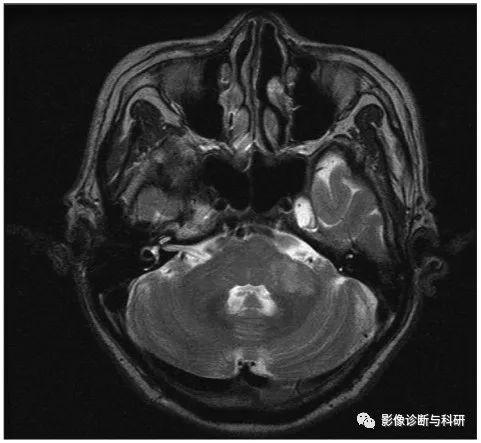

53 岁,男子,眩晕、恶心和呕吐。MR提示小脑后下动脉 (PICA) 分布区高信号,邻近的脑干和第四脑室受到压迫。